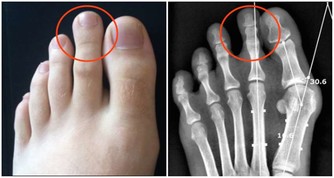

***4、打耳洞需謹慎***

為了戴耳環而打耳洞十分尋常,有的人還同時打好幾個耳洞。但你知道嗎?打耳洞有可能留下疤痕疙瘩,增生的疤痕比原來傷口還大,甚至會長出很大的疤痕疙瘩。臨床上許多患者耳朵上的疤痕疙瘩就是由於穿耳洞造成的,尤其是疤痕體質的人群,要治愈非常難。由於這些疤痕疙瘩要通過手術切除,術後恢復同樣可能形成疤痕,復發率高達50%。